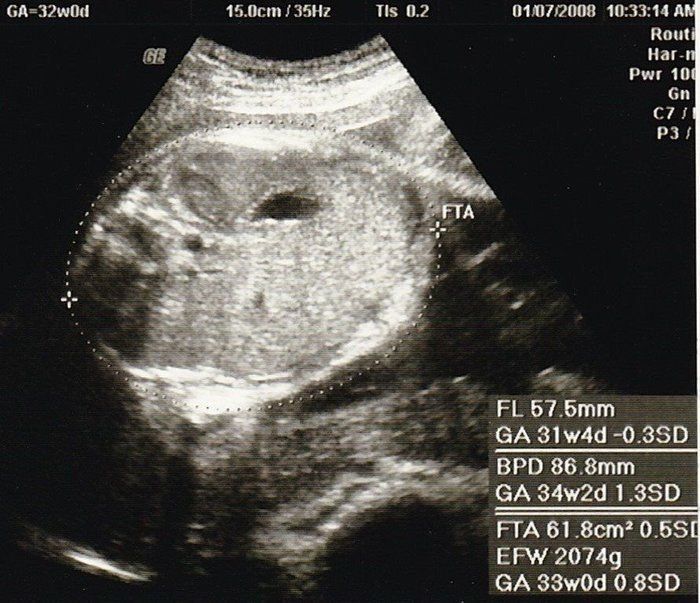

セイコさんの妊娠32週目のエコー写真 少し血圧が高く、浮腫も出てしまう

おなかの中はどうなっていくの? エコー写真で振り返る、高齢ママのはじめての妊娠生活

今日で東京のお医者様の健診は最後です。最後の最後で、血圧がやや高めなことと、少し浮腫みが出てしまって心配をかけてしまいました。娘は順調で、立派な太ももの骨を見せてもらいました。